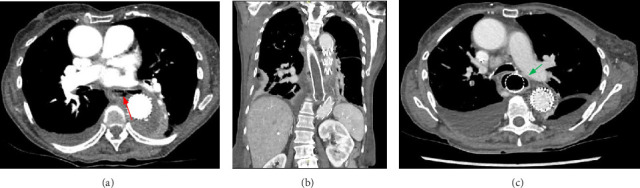

We present a case of an 80-year-old female who presented with chest pain, vomiting and night sweats a few weeks post thoracic endovascular aortic aneurysm repair (TEVAR). A computed tomography (CT) scan demonstrated a type 1B endoleak for which she underwent a repeat TEVAR. Postoperatively, she developed fever, dysphagia, haematemesis and melaena. CT angiography subsequently confirmed an aorto-oesophageal fistula (AEF). Gastroscopy was performed to confirm this and found an ovoid oesophageal perforation with visible aortic graft and purulent fluid. Serial endoscopic oesophageal stents were placed and the patient recovered after an oesophageal Ultraflex stent was placed. Unfortunately, however, the patient was found unresponsive at home with black vomitus and in cardiac arrest and passed away 18 months after her initial endoscopic procedure. This case highlights that AEF is a complication following a TEVAR procedure. This can be managed temporarily with oesophageal stent placement and an Ultraflex stent in the longer term. However, oesophageal stent placement is not curative in cases of significant oesophageal perforation as it does not lead to lead to closure of a large defect.

Abstract Image